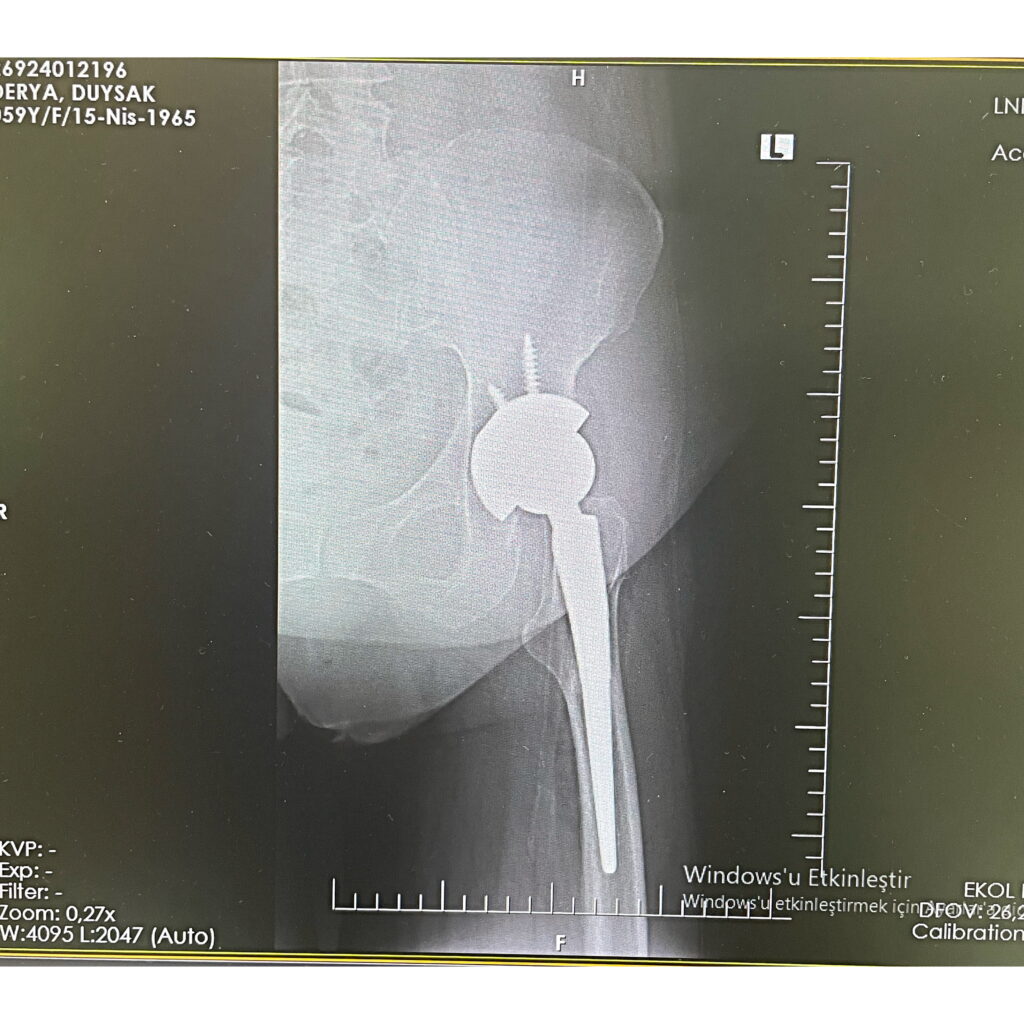

D.D.